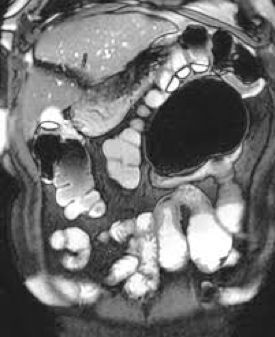

La maladie de Crohn est une maladie intestinale caractérisée par une atteinte inflammatoire granulomateuse de toute la paroi de l’intestin alternant avec des parties saines de l’intestin. L’atteinte inflammatoire transmurale de la maladie de Crohn peut amener à des phénomènes de fibroses, de rétrécissement de l’intestin jusqu’à une clinique d’obstruction de l’intestin. Les conséquences secondaires de l’atteinte transmurale de la maladie de Crohn est le risque d’abcès, de microperforations ou de fistules. L’atteinte la plus fréquente de la maladie de Crohn concerne la partie terminale de l’iléon (80% des cas), on assiste à des atteintes en patchwork avec alternance de parties saines et malades. La photo ci-dessous permet d’imager la différence entre l’atteinte de la colite ulcéreuse qui est caractérisée par une atteinte de la muqueuse du colon partant depuis le rectum et pouvant s’étendre proximalement par rapport à la maladie de Crohn qui est caractérisée par une atteinte transmurale en patchwork pouvant impliquer n’importe qu’elle parties du système digestif avec des risques de sténoses, d’abcès ou de fistules.